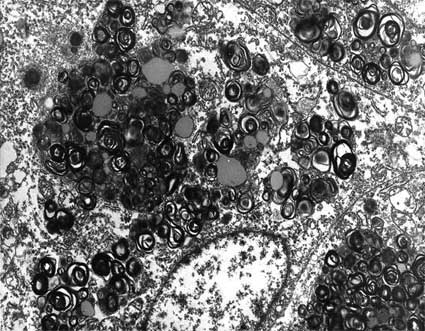

Histopathology

The most striking changes are in glomeruli; The podocytes are large and vacuolated, with hypertrophic appearance and cytoplasm distended by vacuoles that give them a foamy appearance. They are empty in conventional cuts from paraffin- embedded tissue because the GSL are lost with routine processing. If the tissue is pretreated with osmium the GSL are conserved. In freeze-cut material (still fixed in formaldehyde), intracytoplasmic inclusions appear birefringent, autofluorescent and sudanophilic, they are also positive with the PAS. We can also find this material in mesangial, tubular and interstitial cells. In the endothelium of arteries and arterioles there are cytoplasmic inclusions and, as an important feature, there is usually no renal endothelial cell involvement in the cardiac variant of the disease, this would help to differentiate it from the renal variant, where they are abundant. Other renal changes are nonspecific and are related to chronic damage.

Figure 12. In Fabry's disease, the vacuolated aspect of podocytes is very characteristic, which gives a very particular appearance to the glomeruli (arrows). We can also see vacuolated cells in the tubular epithelium, Bowman's capsule and in endothelium. (Masson's trichrome, X400).

Electron Microscopy

There is osmophilic material, laminated, similar to myelin bodies; they are mainly found in podocytes, epithelium of Bowman's capsule, tubular epithelium and endothelium, although they can be seen in any type of cells. Myelin-like bodies have a periodicity of 4 to 10 nm.

Figure 15. Electron microscopy of the same case of the three previous microphotographs showing a podocyte with laminated structures in its cytoplasm: "myelin bodies". (Electron microscopy, original magnification, X4,000).